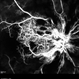

- Dengue maculopathy

Scanning laser ophthalmoscope

NIDEK SLO MIRANTE - Description

- Dengue maculopathy healing phase.